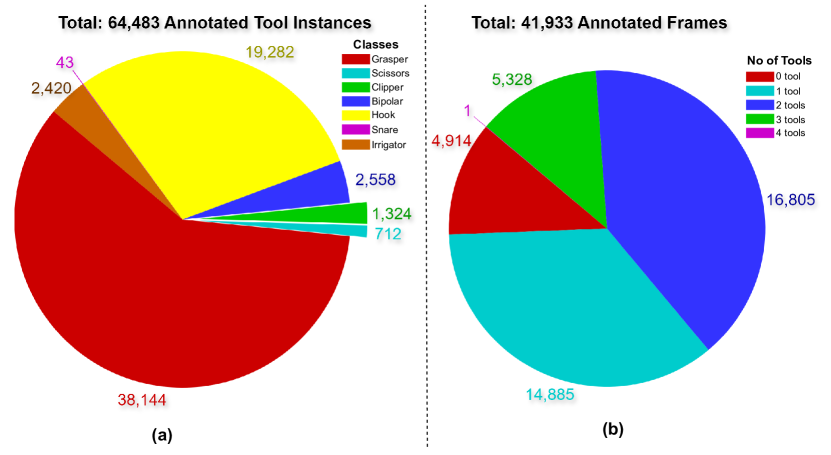

Tool Class Distribution

Figure 7(a) shows the distribution of tool classes across the entire dataset. Graspers are the most frequently used tools, followed by hooks. Tools like irrigators, clippers, scissors, and bipolars are used less frequently, with snares being the least used. This indicates a high imbalance in tool class occurrences.

Tool Instance Distribution per Frame

Figure 7(b) illustrates the number of tool instances per frame. The majority of frames contain one or two tools, with a maximum of four tools in a single frame. Approximately 5,328 frames (about one-eighth of the dataset) contain no tools.

Partition and Sequence Analysis

Table 2 provides a summary of the number of sequences, number of frames and amount of annotated tools in each of the dataset partitions. Figure 8 provides an analysis of tool instances across different sequences and their partitions. Instance-CholecT50-full has the highest number of tool instances, whereas Instance-CholecT50-sparse has the fewest. This figure highlights the imbalance between densely and sparsely annotated sequences and the presence of a sequence with no tools in Instance-CholecSeg8k.